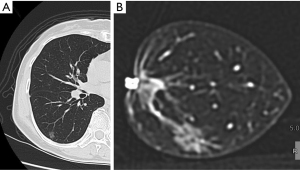

The resected specimens were inflated by the careful instillation of air. Puncture was performed at a distant site, where the pulmonary lesion was absent, using a 23-G puncture needle connected to an appropriately sized syringe. The instillation was done slowly in order to prevent alveolar wall destruction. The degree of inflation differs among specimens because air leak from the puncture site or stapled site eventually develops. After the specimen was placed in a plastic container, the specimen along with the container underwent conventional 64-detector CT (Revolution GSI; GE, Chicago, IL, USA) as soon as possible. The scan parameters were as follows: tube voltage, 80 kV; rotation time, 0.6 s; beam width, 20 mm; pitch, 1.375; slice thickness, 0.625 mm; slice interval, 0.625 mm; scan field of view (FOV), 8 cm; matrix, 512×512; recon type, HD Lung; noise index, 10. It generally takes 5 minutes or less for scanning of the resected specimen and image acquisition. The obtained images were evaluated intraoperatively in the operating room on multi-planner reconstruction images. Figures 1-3 show two representative cases with primary lung cancer.

We established a reliable procedure for confirming during surgery whether or not the resection line had been appropriate without cutting the resected specimen, even for impalpable tumors. We must occasionally make multiple sections from resected specimens if the tumor is impalpable, which compromises the subsequent pathological examination of the invasiveness of primary lung adenocarcinoma as well as the accurate measurement of the surgical margin. In our current initial clinical experience, the presence of an intrapulmonary small lesion (consolidation diameter ≤1 cm) within the resected specimen was able to be confirmed in all patients, including two with lesions representing purely ground-glass attenuation (Case 1 and 2). Furthermore, the surgical margin length was able to be accurately measured. The further accumulation of data concerning the surgical margin as assessed via intraoperative CT, together with information on the prognostic outcomes, will provide reliable evidence regarding the necessary surgical margin for small lung cancer, which still remains controversial.

One of the most important benefits of the present method is that we can measure the distance between the intrapulmonary lesions and any staple line (Figure 2) on multiplanar reconstruction images. This means that we can create multiple section images of the resected specimens without cutting the specimen itself, which can aid in determining how to make additional cut lines during performing additional resection for insufficient surgical margin.